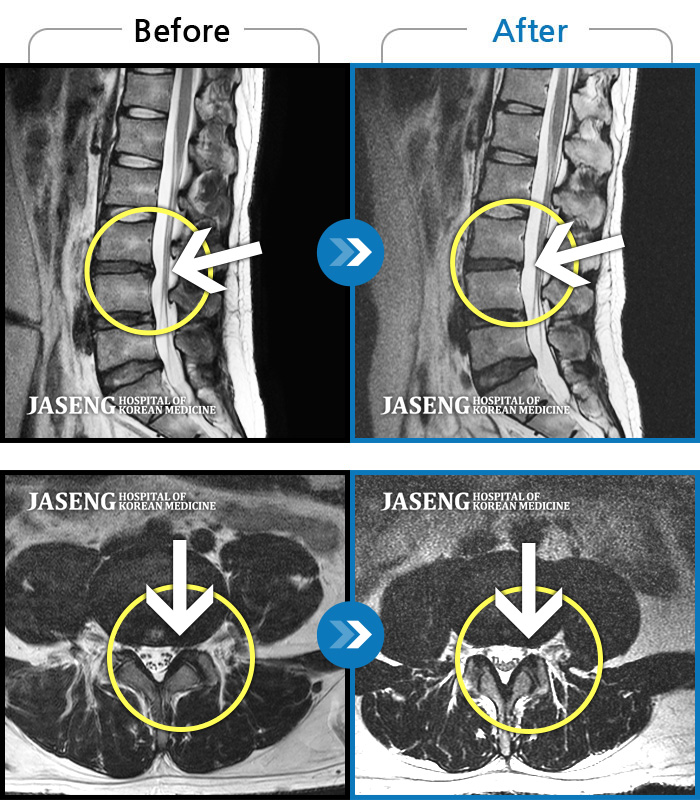

푸쉬업을 여러 번 반복한 뒤 극심한 하요부 통증 및 우측 하지부 저림

2024.03.21 ~ 2024.09.23